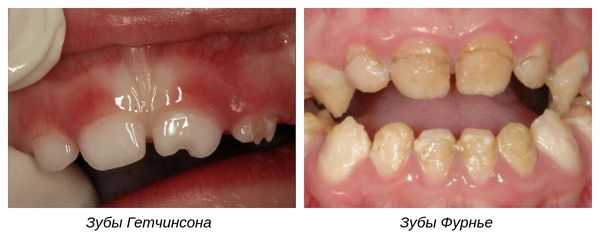

- Зубы Гетчинсона. При данной патологии верхние центральные резцы имеют отверткообразную или бочкообразную форму. Их размер у шейки несколько больше, чем у режущей поверхности и имеется полулунная выемка у режущего края. Ранее полагалось, что данный симптом наблюдается только при врожденном сифилисе, однако позже установили, что аномалия возникает и при иных причинах.

- Зубы Фурнье. Клинически выглядят так же, как и при симптоме Гетчисона, но без полулунной выемки.

Зубы Гетчинсона

Характеризуются отверткообразной или бочкообразной формой и особой полулунной выемкой на режущем крае. Основание зуба при этом намного шире, чем коронковая часть, а эмаль может присутствовать только на углах режущего края зуба. Данная аномалия наблюдается на верхних центральных резцах; вместе с паренхиматозным кератитом и специфическим лабиринтитом она входит в так называемую триаду Гетчинсона - набор достоверных признаков позднего врожденного сифилиса. До времени прорезывания постоянных зубов патологические изменения можно выявить при помощи рентгенографии.

Зубы Фурнье

Центральные резцы, имеющие отверткообразную форму, практически не отличаются от зубов Гетчинсона за исключением отсутствия характерной полулунной выемки на режущем крае. Подобно зубам Гетчинсона, зубы Фурнье относятся к симптоматике наследственного сифилиса.

- Зубы Гетчинсона — аномалия, при которой коронки центральных верхних резцов имеют отвёрткообразную форму с полулунными вырезками по режущим краям [9] .

- Зубы Фурнье — зубы бочковидной формы без полулунной вырезки, шейки которых больше режущих краёв.